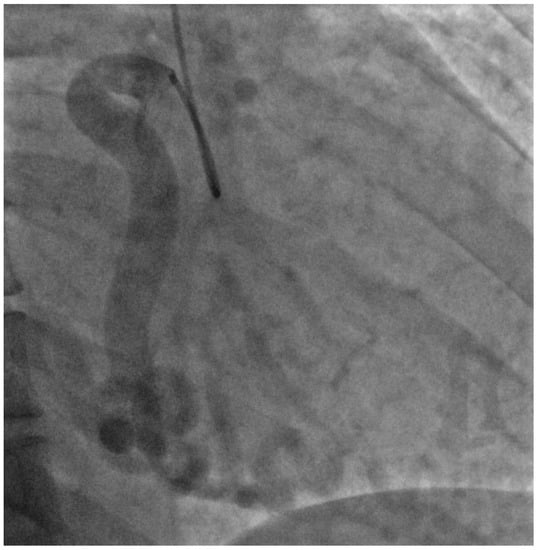

For further assessment, she underwent cardiac Magnetic Resonance Imaging (MRI) to investigate a possible cardiomyopathy. This showed dilatation of the left ventricle and an ejection fraction of 51%. Late gadolinium enhancement sequences also found a previous myocardial infarction in the LAD territory. In view of the cardiac MRI findings, she had a diagnostic coronary angiogram. This showed a large aneurysmal right coronary artery of normal origin but the left coronary artery could not be cannulated, suggesting an aberrant origin (Figure 4).

Figure 4.

Angiographic image of the coronary circulation and collaterals. Right coronary artery appears dilated and tortuous with collaterals following across to the left side of the heart.